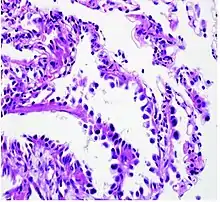

Histopathology of lepidic predominant adenocarcinoma.

• lepidic predominant [18]

Cell patterns identifying subtypes are associated with prognosis, ranging from favorable (lepidic) to intermediate (acinar and papillary) to poor (micropapillary and solid).[2]

Adenocarcinoma of the lung tends to stain mucin positive as it is derived from the mucus-producing glands of the lungs. Similar to other adenocarcinoma, if this tumor is well differentiated (low grade) it will resemble the normal glandular structure. Poorly differentiated adenocarcinoma will not resemble the normal glands (high grade) and will be detected by seeing that they stain positive for mucin (which the glands produce). Adenocarcinoma can also be distinguished by staining for TTF-1, a cell marker for adenocarcinoma.[29]

As discussed previously, the category of adenocarcinoma includes are range of subtypes, and any one tumor tends to be heterogeneous in composition. Several major subtypes are currently recognized by the World Health Organization (WHO)[1] and the International Association for the Study of Lung Cancer (IASLC) / American Thoracic Society (ATS) / European Respiratory Society (ERS):[30][31][32] lepidic predominant adenocarcinoma, acinar predominant adenocarcinoma, papillary predominant adenocarcinoma, micropapillary predominant adenocarcinoma, solid predominant adenocarcinoma, and solid predominant with mucin production. In as many as 80% of these tumors, components of more than one subtype will be recognized. Surgically resected tumors should be classified by comprehensive histological subtyping, describing patterns of involvement in increments of 5%. The predominant histologic subtype is then used to classify the tumor overall.[2] The predominant subtype is prognostic for survival after complete resection.[33]

To reveal the adenocarcinomatous lineage of the solid variant, demonstration of intracellular mucin production may be performed. Foci of squamous metaplasia and dysplasia may be present in the epithelium proximal to adenocarcinomas, but these are not the precursor lesions for this tumor. Rather, the precursor of peripheral adenocarcinomas has been termed atypical adenomatous hyperplasia (AAH).[10] Microscopically, AAH is a well-demarcated focus of epithelial proliferation, containing cuboidal to low-columnar cells resembling club cells or type II pneumocytes.[10] These demonstrate various degrees of cytologic atypia, including hyperchromasia, pleomorphism, prominent nucleoli.[10] However, the atypia is not to the extent as seen in frank adenocarcinomas.[10] Lesions of AAH are monoclonal, and they share many of the molecular aberrations (like KRAS mutations) that are associated with adenocarcinomas.[10]